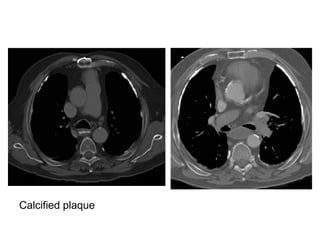

Calcified plaque